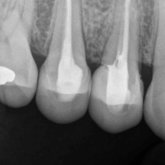

He received his Diploma in Implantology in 2016 from the University of Pretoria, which he passed with Distinction. He is also a member of the International Team for Implantology (ITI), which is based in Switzerland and offers members access to the latest research and cutting-edge techniques.